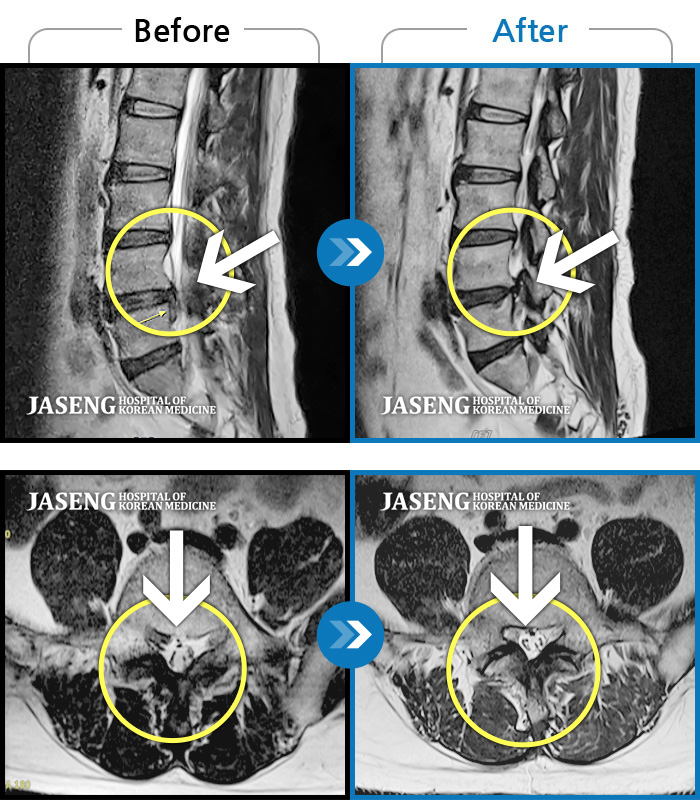

Before

After

환자에게 사전 동의를 받아 동일 조건에서 촬영되었습니다.

개인에 따라 치료 후 부작용이 발생할 수 있으니 의료진과 상담 후 치료를 진행하시기 바랍니다.

서 있거나 보행시 엉덩이 통증

우측 허리통증 및 우측 엉치부터 발목외측까지 통증과 저림 증상